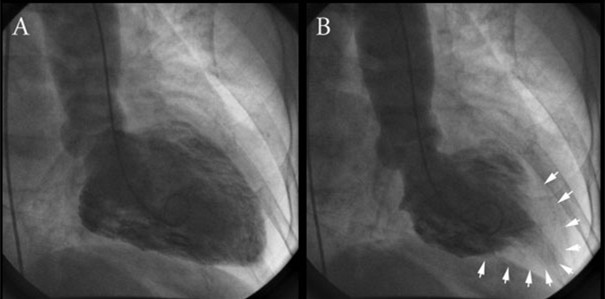

左心室造影显示出舒张期(A)及收缩期末(B)LV中部和心尖部的典型形态。在收缩期末,心尖部和LV下段(箭头所示)可明显看到动脉瘤样扩张(气球样);因此,TCM也被称为“心尖球形综合征”。

收缩期左心室造影显示特性心尖部球样扩张伴心尖室壁运动缺失(箭头)。